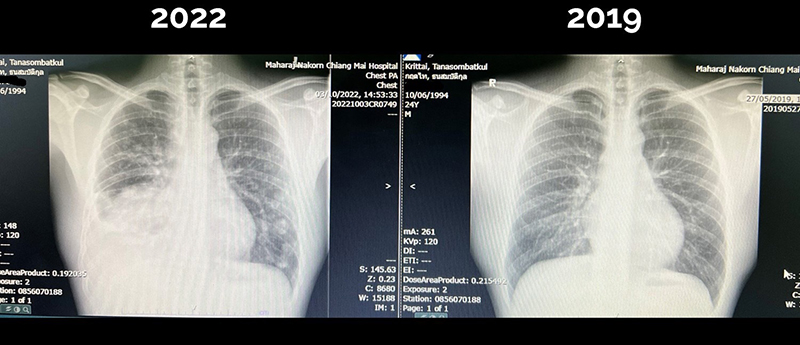

จากกรณีที่คุณหมอกฤตไท ธนสมบัติกุล เล่าเรื่องราวชีวิตการเป็นหมอที่กำลังจะรุ่งโรจน์ ได้รับการบรรจุเป็นอาจารย์หมอมาแล้ว 2 เดือน ชีวิตส่วนตัวก็กำลังจะแต่งงาน แต่กลับเกิดเหตุพลิกผัน เมื่อคุณหมอกลับพบว่าตัวเองเป็นมะเร็งปอดระยะสุดท้ายในวัย 28 ปี ทั้งที่กิจวัตรประจำวันชอบออกกำลังกาย ดูแลสุขภาพตัวเองมาโดยตลอด